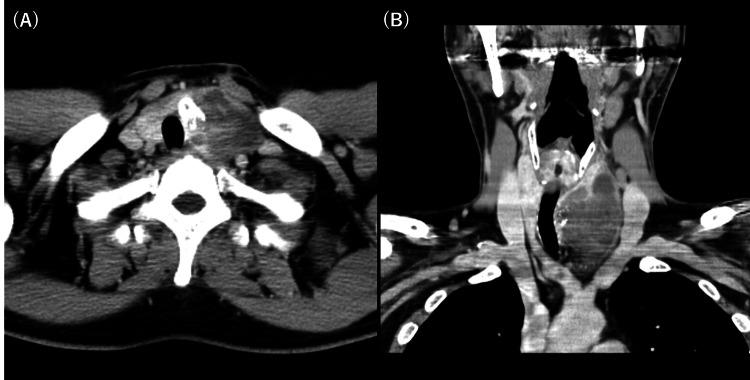

Anaplastic thyroid carcinoma, a rare type of primary thyroid cancer, is one of the most aggressive neoplasms with a poor prognosis. Many cases are in the advanced stage at the time of the initial visit, and curative treatment is impossible. Because of the highly radioresistant nature of anaplastic thyroid carcinoma, this condition cannot be properly controlled with conventional radiotherapy. Herein, we report the case of a patient with anaplastic thyroid carcinoma who underwent hypofractionated radiotherapy, attained a complete response, and is still alive more than 10 years after treatment with no evidence of disease. To overcome the high radioresistance of anaplastic thyroid carcinoma, we administered 50 Gy in 10 fractions three times a week. Furthermore, we administered paclitaxel and carboplatin sequentially before and after radiotherapy. Consequently, the patient completed treatment and reached a complete response. He is still alive more than 10 years after treatment with no evidence of disease or severe adverse events. Hypofractionated radiation therapy may provide good control of locally advanced anaplastic thyroid carcinoma.

间变性甲状腺癌是一种罕见的原发性甲状腺癌,是最具侵袭性的肿瘤之一,预后较差。许多病例在初诊时就已处于晚期,无法进行根治性治疗。由于间变性甲状腺癌具有高度放射抗性,传统放疗无法有效控制这种疾病。在此,我们报告一例间变性甲状腺癌患者,该患者接受了大分割放疗,获得了完全缓解,并且在治疗后存活超过10年,无疾病迹象。为克服间变性甲状腺癌的高放射抗性,我们每周三次,分10次给予50 Gy的剂量。此外,我们在放疗前后序贯给予紫杉醇和卡铂。结果,患者完成治疗并达到完全缓解。治疗后他存活超过10年,无疾病迹象或严重不良事件。大分割放射治疗可能对局部晚期间变性甲状腺癌有良好的控制效果。